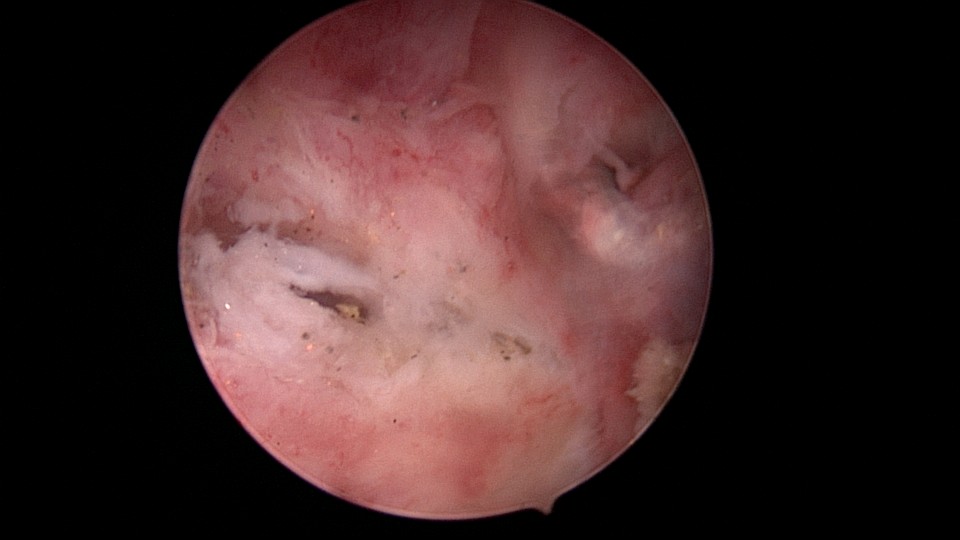

患者49岁,G1P1,顺产1次。安环13年,月经紊乱1月,外院取环失败。B超提示O型环嵌顿,宫腔镜见宫颈管及宫腔组织充血,宫腔广泛粘连,节育环嵌顿、扭曲,异物钳配合中弯钳拉出节育环,环变形、断裂,宫壁节育环嵌顿处见割裂痕迹,无出血,检查宫腔各部,无节育环残留。